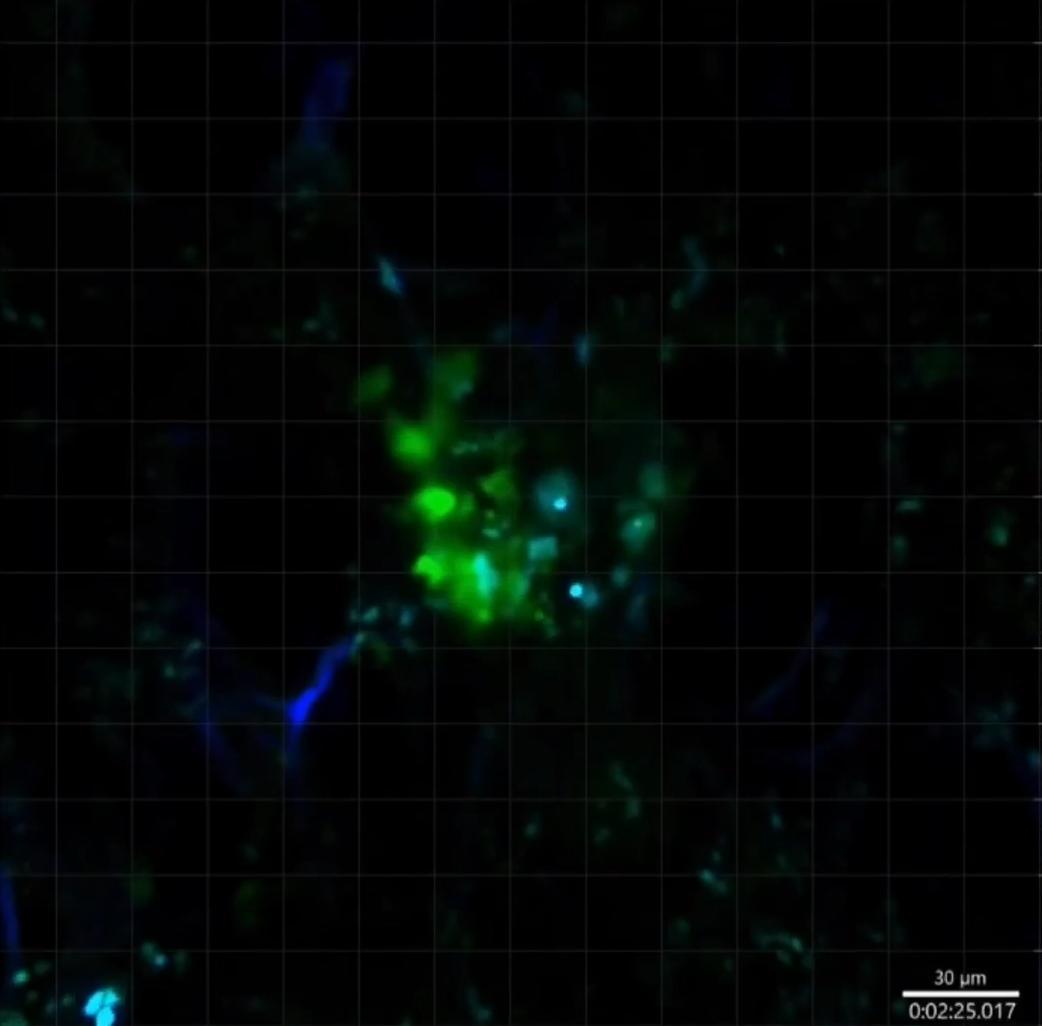

他們首先分析了重症新冠患者的血液樣本, 然後在實驗鼠身上測試了四種不同類型的癌症,包括黑色素瘤、肺癌、乳腺癌、結腸癌等,結果令人振奮:通過藥物模擬新冠感染的免疫反應,這些實驗鼠體內的腫瘤確實開始縮小了!